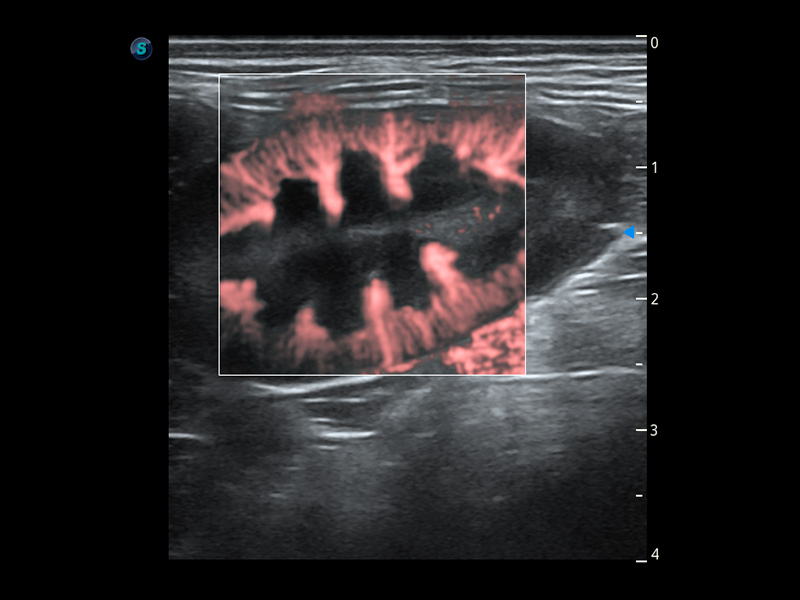

PDI 能量多普勒血流

提供高灵敏度和空间分辦率的血流图像,获得更加真实和丰富的诊断信息。

SR Flow 高分辨率血流成像

能够清晰显示细小、低速血流图像,获取传统彩色多普勒技术难以得到的细节和信息。

Micro F 显微血流成像

通过创新的Matrix E自适应滤波器和超长时间域算法,极大提升超低速微细血流的检出能力,同时更精准地滤除软组织和噪声信号,为兽用医生提供以往无法通过常规血流获得的疾病诊断信息。